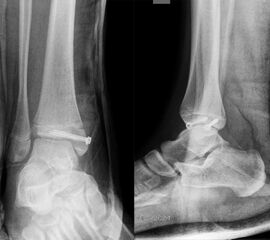

Fugengelenkfrakturen treten typischerweise vor dem 10. Lebensjahr auf, in einer Phase, in welcher die Wachstumsfugen noch weit offen sind. Dieser Frakturtyp betrifft fast ausschließlich den medialen Malleolus. Laterale Frakturen sind extrem selten, teilweise kommt es zu lateralen Bandverletzungen oder Fugenschaftfrakturen der distalen Fibula. Die Frakturlinie verläuft in einer Verlängerungslinie von der medialen Taluskante nach proximal. Häufig stellen sich Verletzungen des Innenknöchels im Röntgenbild schlechter dar, insbesondere wenn die Aufnahmen verdreht sind oder die Ebene der Fraktur bei geringer Dislokation verkippt zur Röntgenebene liegt. Besteht klinisch der geringste Hinweis auf eine Verletzung des Innenknöchels, muss aufgrund der Tragweite der Verletzung durch entsprechende Aufnahmen gegebenenfalls auch Schnittbildverfahren die Verletzung sicher diagnostiziert oder ausgeschlossen werden (Abb. 15).